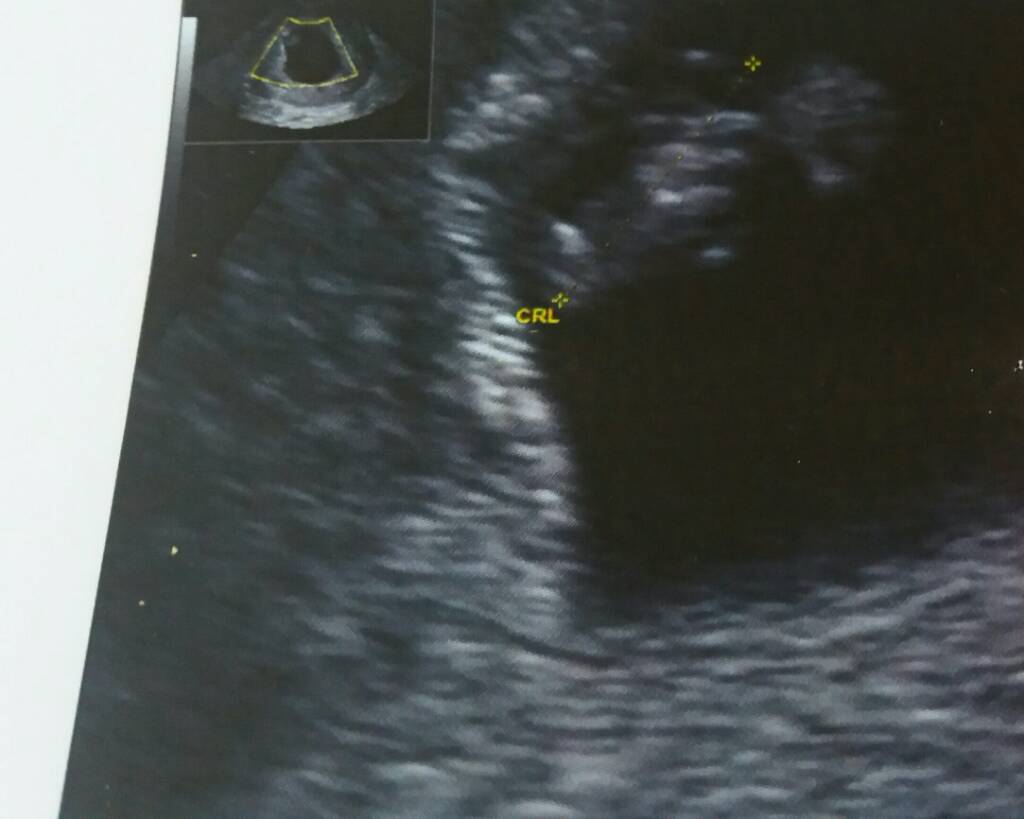

Gratulacje [emoji7] [emoji7] [emoji7]Hej ja już po usg[emoji4]wszystko dobrze.moje szczęście ma 1 cm.serduszko bije[emoji1]Zobacz załącznik 882881

Jaki cudny mały człowiek . GratulujeHej ja już po usg[emoji4]wszystko dobrze.moje szczęście ma 1 cm.serduszko bije[emoji1]Zobacz załącznik 882881

Piękności malutkieHej ja już po usg[emoji4]wszystko dobrze.moje szczęście ma 1 cm.serduszko bije[emoji1]Zobacz załącznik 882881

Super wieści !!!Hej ja już po usg[emoji4]wszystko dobrze.moje szczęście ma 1 cm.serduszko bije[emoji1]Zobacz załącznik 882881